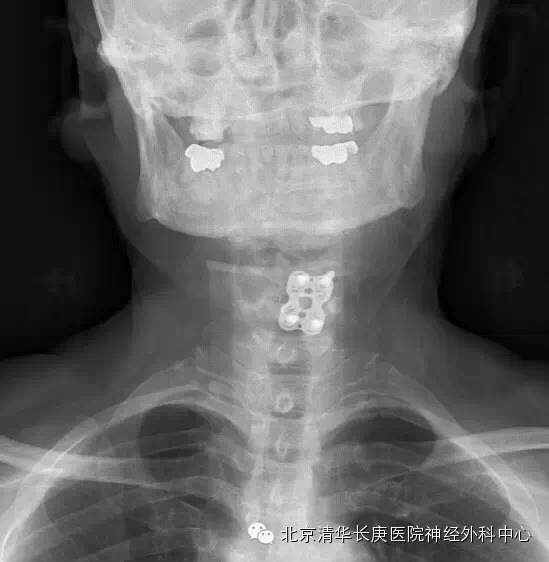

术中O-ARM及导航联合精准定位及内固定

术中、后O-ARM确定:C5-6前路板固定良好